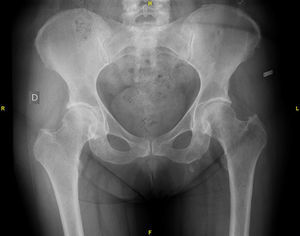

The study of the extension of the disease included BS, which revealed the presence of a diffuse blastic lesion in the sternal manubrium, suggestive of Paget's disease or a metastatic lesion (Fig. 1). The study was completed with radiographs of chest, lumbosacral spine and pelvis (Figs. 2 and 3), in which the only finding was increased density in L4-L5 facet joints. Chest CT, recommended by the professionals in nuclear medicine, revealed sclerosis in the sternal manubrium, suggestive of metastasis (Fig. 4).